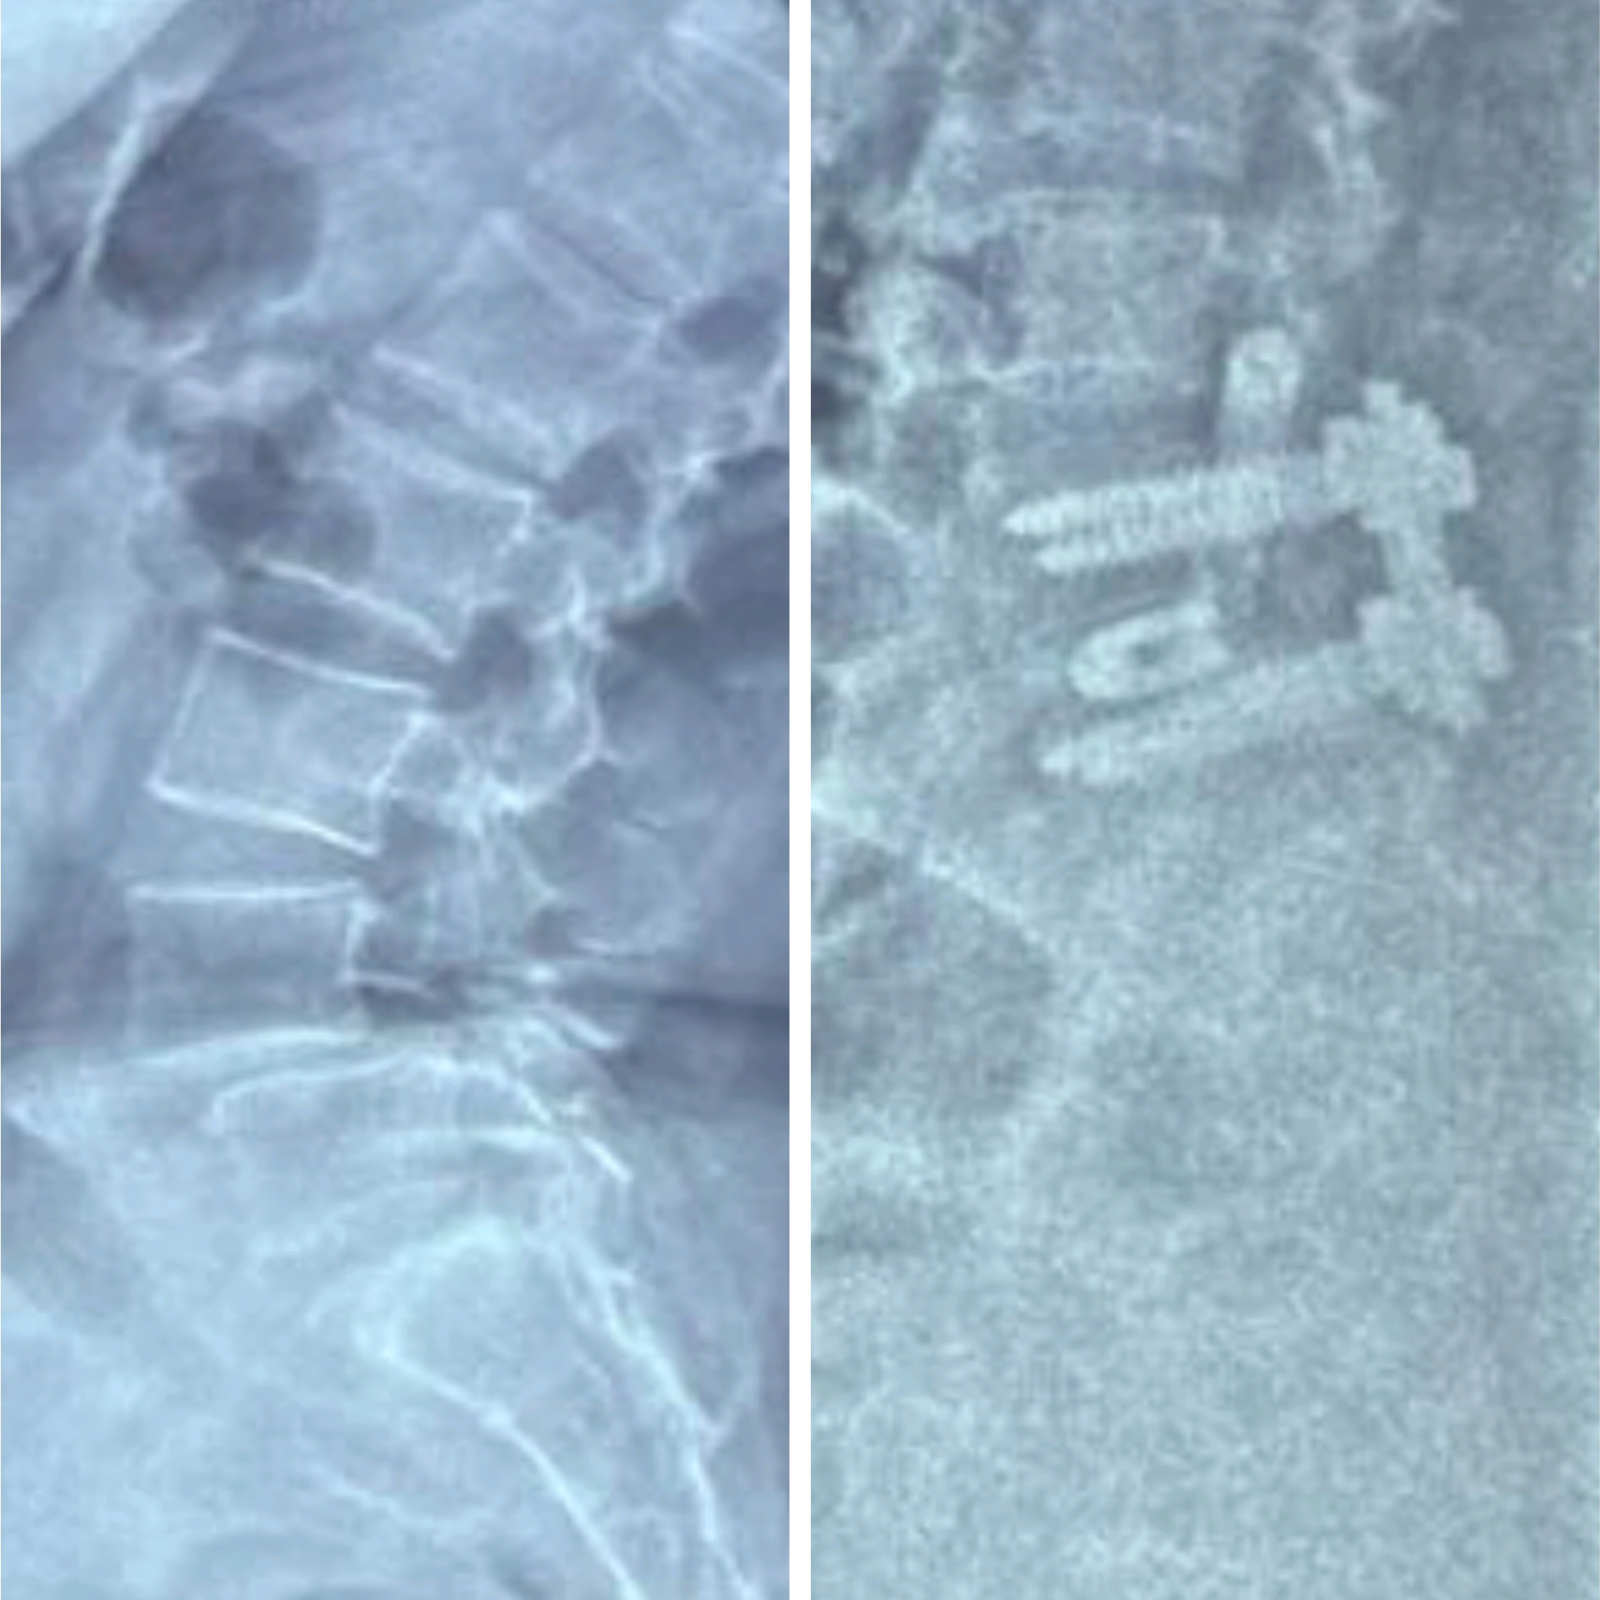

TLIF for L45 Spondylolisthesis- Spinal fusion Surgery